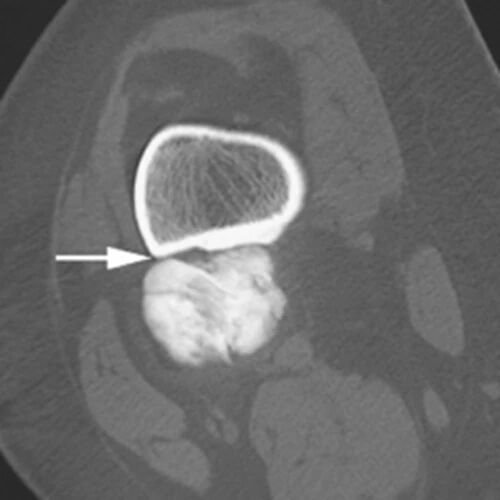

肿瘤内液 - 液平面

肿瘤内液-液平面多数是病灶内囊变出血所致,MRI T2W1 为上部呈高信号下部呈中低信号的液-液平面。CT 可为上部低密度下部高密度的液-液平面(图 32)。液-液平面常见于动脉瘤样骨囊肿、但也可见于骨内腱鞘囊肿(图 33)、囊性血管瘤病等其他肿瘤和肿瘤样病变。

图 32.肿瘤内液-液平面:动脉瘤样骨囊肿